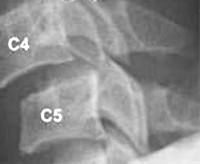

Рентгенологическое исследование является основным методом диагностики. Шейный отдел позвоночника исследуется в пяти проекциях:

• переднезадняя проекция;

• боковая;

• снимки в боковой проекции со сгибанием и разгибанием головы;

• прямой снимок через открытый рот.[3]

Этот стандарт исследования минимизирует возможность ошибок диагностики, так как подвывих иногда выявляется только на функциональных снимках. Исследование шейного отдела позвоночника в двух или трех стандартных проекциях не дает достаточной информации, чтобы диагностировать подвывих атланта, который часто остается нераспознанным.[4]

Для исследования грудного и поясничного отдела используются переднезадняя и боковая проекции, включая снимок со сгибанием и разгибанием. В ряде случаев дополнительно проводится МРТ или КТ позвоночника, при осложнениях — электромиография и ультразвуковое исследование сосудов головного мозга.[12]